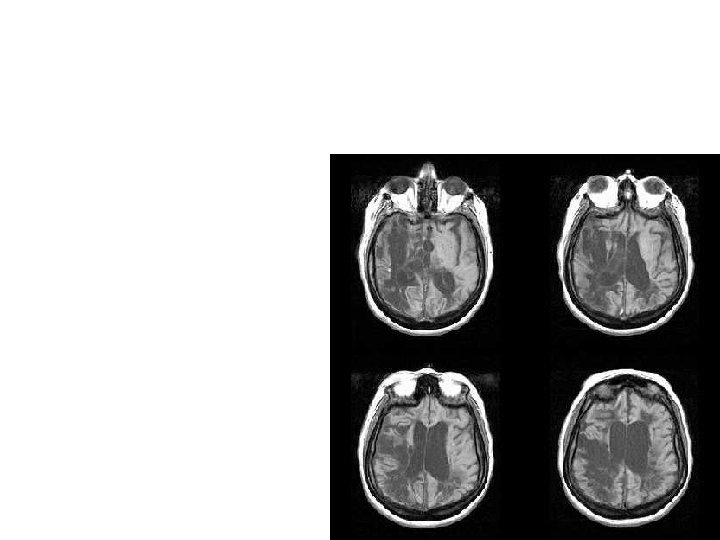

Techniques to examine functions of the brain 1. Remove part of the brain & see what effect it has on behavior 2. Examine humans who have suffered brain damage

3. Stimulate the brain 4. Record brain activity